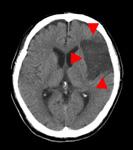

頭部CT検査

十数秒の撮影で、脳内の状態を知ることできます。

画像例では、脳の正常部分に対して白く描出されている部分があることで、脳内出血、くも膜下出血が起きていることがわかります。

反対に、黒く描出されている部分があることで、脳梗塞が起きていることがわかります。

画像の濃淡を調整すると、頭蓋骨骨折の有無を確認することもできます。

また、造影剤を注射しながら撮影することで、動脈瘤や腫瘍などのより詳細な観察が可能になります。